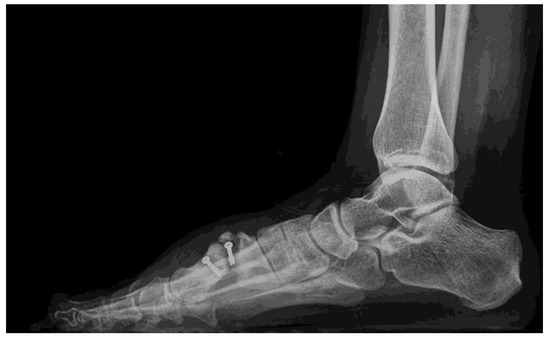

1. Introduction

2. Case Report

2.1. Surgical Procedure

2.2. Postsurgical Procedure and Evolution

2.3. Results